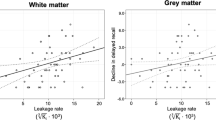

PS was inversely related to cognition assessed as the MoCA score for the temporal cortex, frontal, parietal, temporal and occipital WM, putamen, pallidum and the hippocampus (Table 2). When evaluating hippocampal PS and region-averaged PS values for the cortex, WM and basal ganglia, PS was related to MoCA score for the hippocampus (β = – 2.9 change in MoCA per 1.0 × 10−3 min−1 change in PS; p = 0.006), WM (β = – 2.6; p = 0.04), basal ganglia (β = – 2.3; p = 0.04), and borderline-related for cortex (β = – 2.7; p = 0.08) (Fig. 4). These findings were not suppressed but slightly more pronounced and significant for all regions when adjusting for age and sex (Fig. 4). Further, whole-brain PS was also linked to MoCA in unadjusted (β = – 2.7; p = 0.04) and age and sex adjusted (p = 0.03) models, and similar results were obtained when excluding early frames before the Patlak fit (Sup. Fig. 2), and when excluding the frontal and parietal cortex to minimize errors due to a non-uniform RF pulse excitation profile near the edges of the axial slab (Sup. Fig. 3–4). Hence, while our findings do support a link between BBB leakage and cognition in old age, they also suggest that this effect is a brain wide mechanism rather than an isolated effect in the hippocampus.

Permeability-surface area product (PS; 10−3 min−1) in relation to the Montreal cognitive assessment (MoCA) score for cortex and white matter (WM) lobes, average over frontal, parietal, temporal, occipital and cingulate regions, for basal ganglia (BG), averaged over caudate, putamen and pallidum, and for hippocampus and whole-brain, averaged over all 15 regions. The adj. was adjusted for age and sex by residualization. The β coefficients indicate change in MoCA score per 1.0 × 10−3 min−1 change in PS.